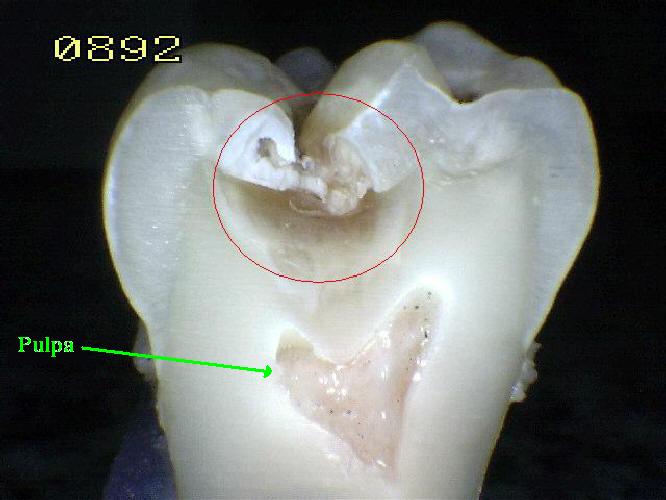

La

Pulpa dental es un órgano junto con la

dentina altamente organizado. (Órgano dentno

pulapar)

Con funciones:

-

de reparación, como es la

producción de dentina secundaria.[14]

Metabólicas e

inmunitasrias [22]

A lo largo del borde

entre la dentina y la pulpa hay células en

empalizada llamada odontoblastos, que

inician la formación de dentina. [21

Su estructura principal

son fibroblastos con una red proteica de

fibrina laxa y vascular arteriovenosa con

fibras nerviosas desmielinizadas

sensitivas.[14]

. La pulpa se llama

comúnmente "el nervio" del diente.